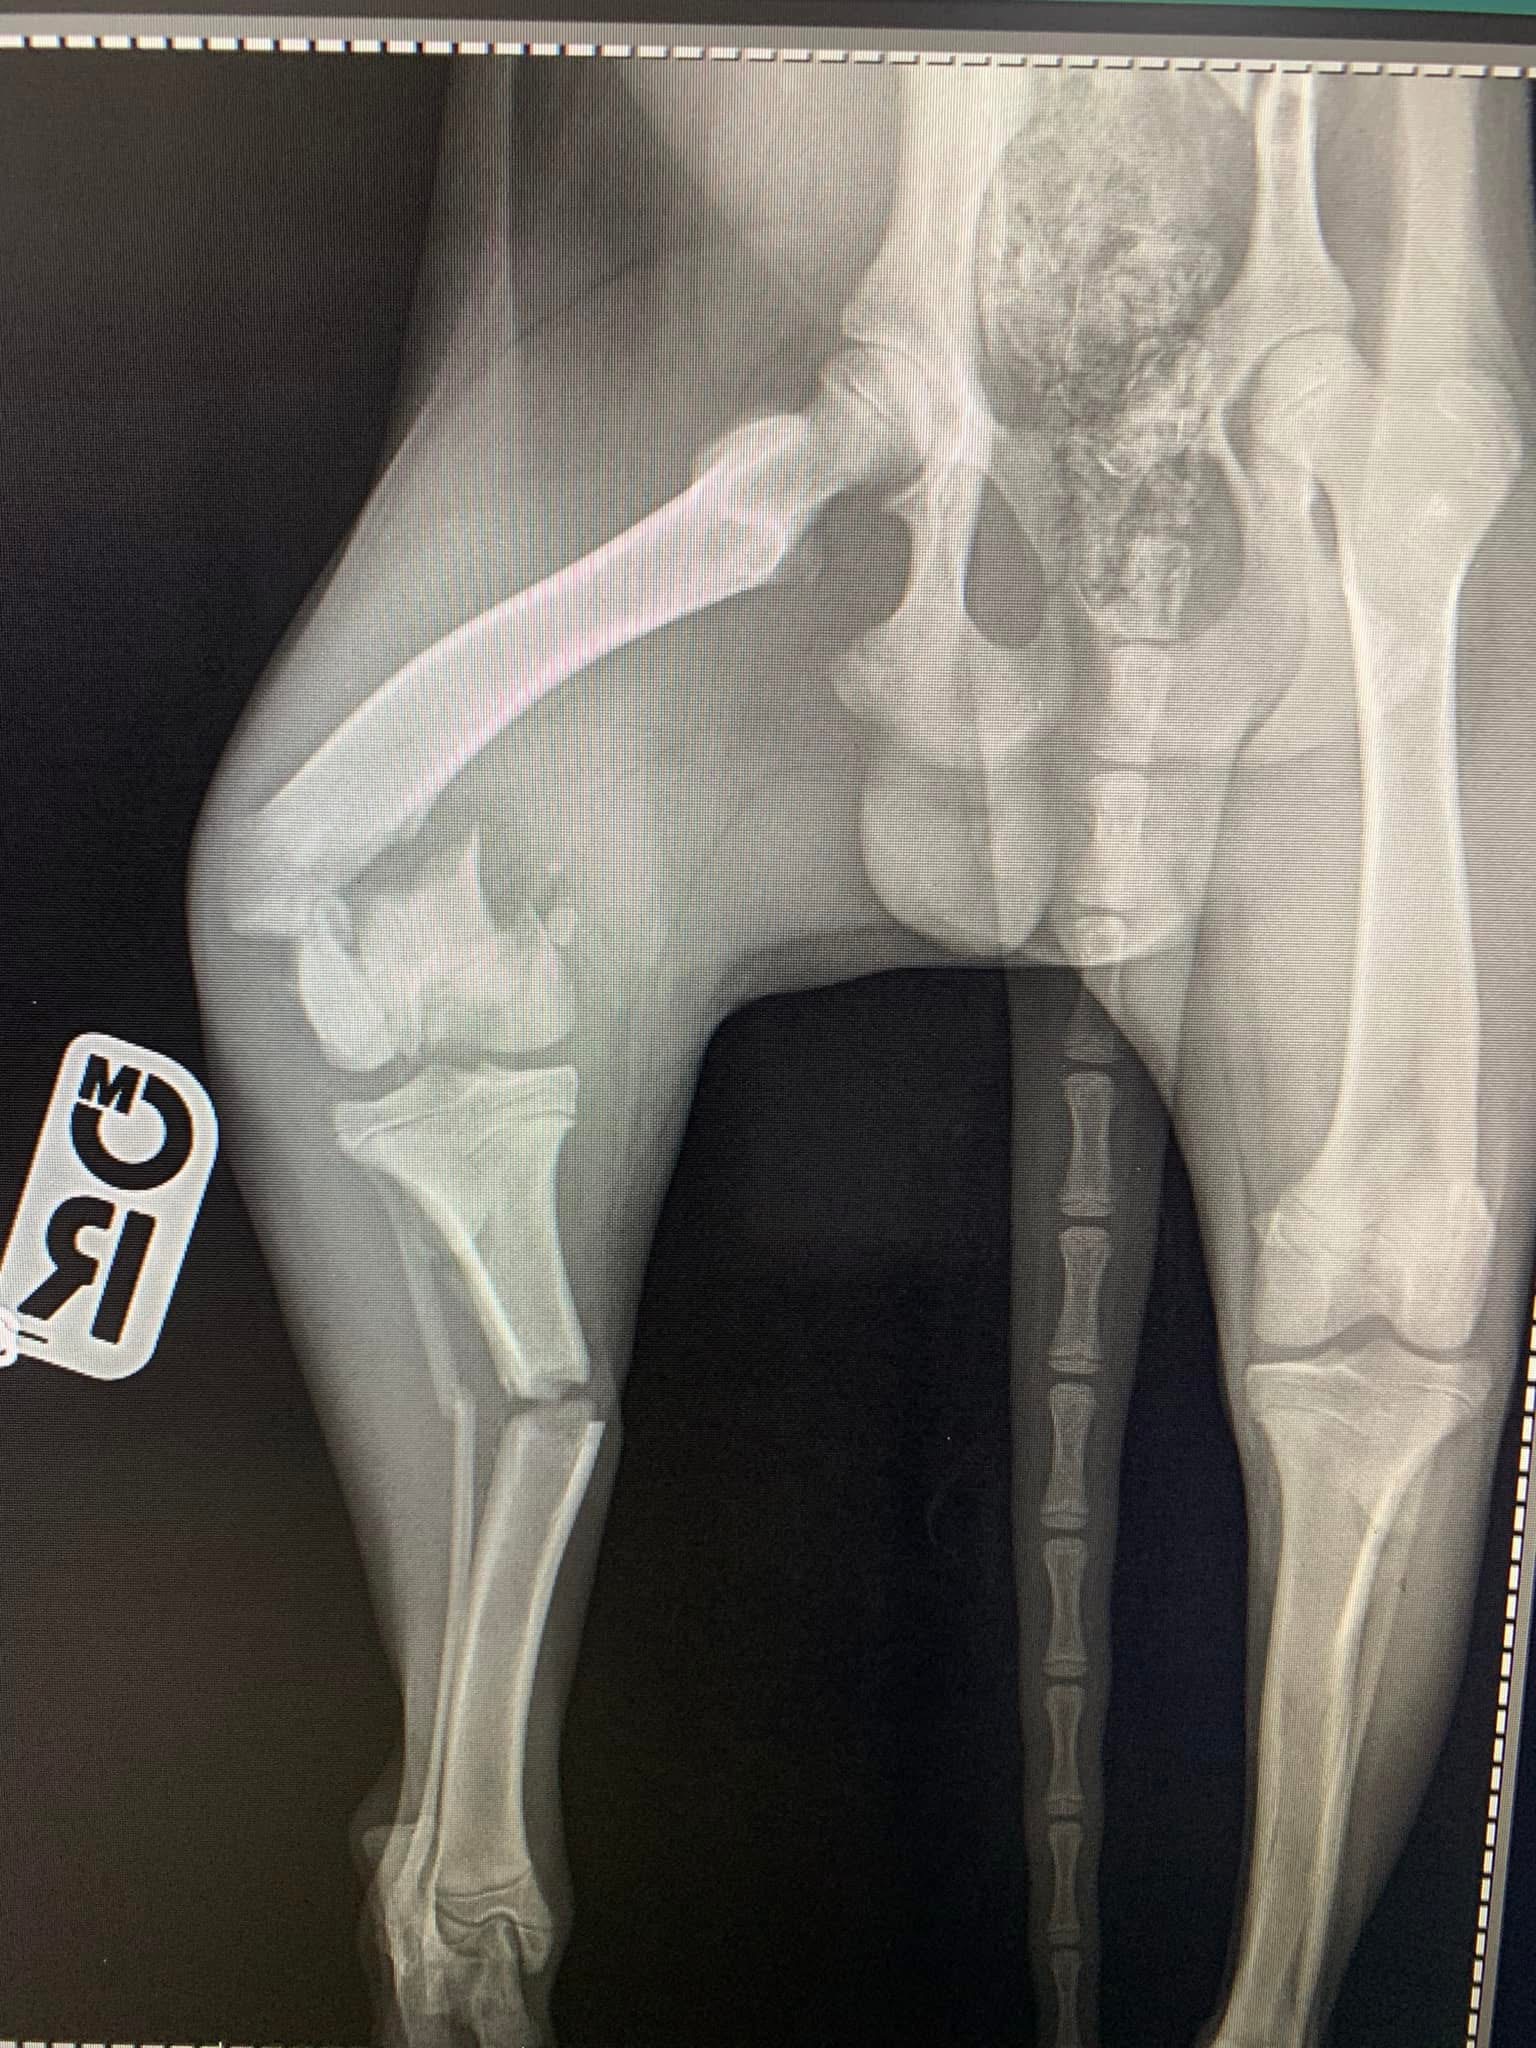

- Liječenje prijeloma kostiju, uključujući intraartikularne frakture

- Hirurške intervencije na zglobovima(artrotomija, artrodeza)

- Liječenje rupture prednjeg križnog ligamenta koljena TPLO (eng. Tibial Plateau Leveling Osteotomy)